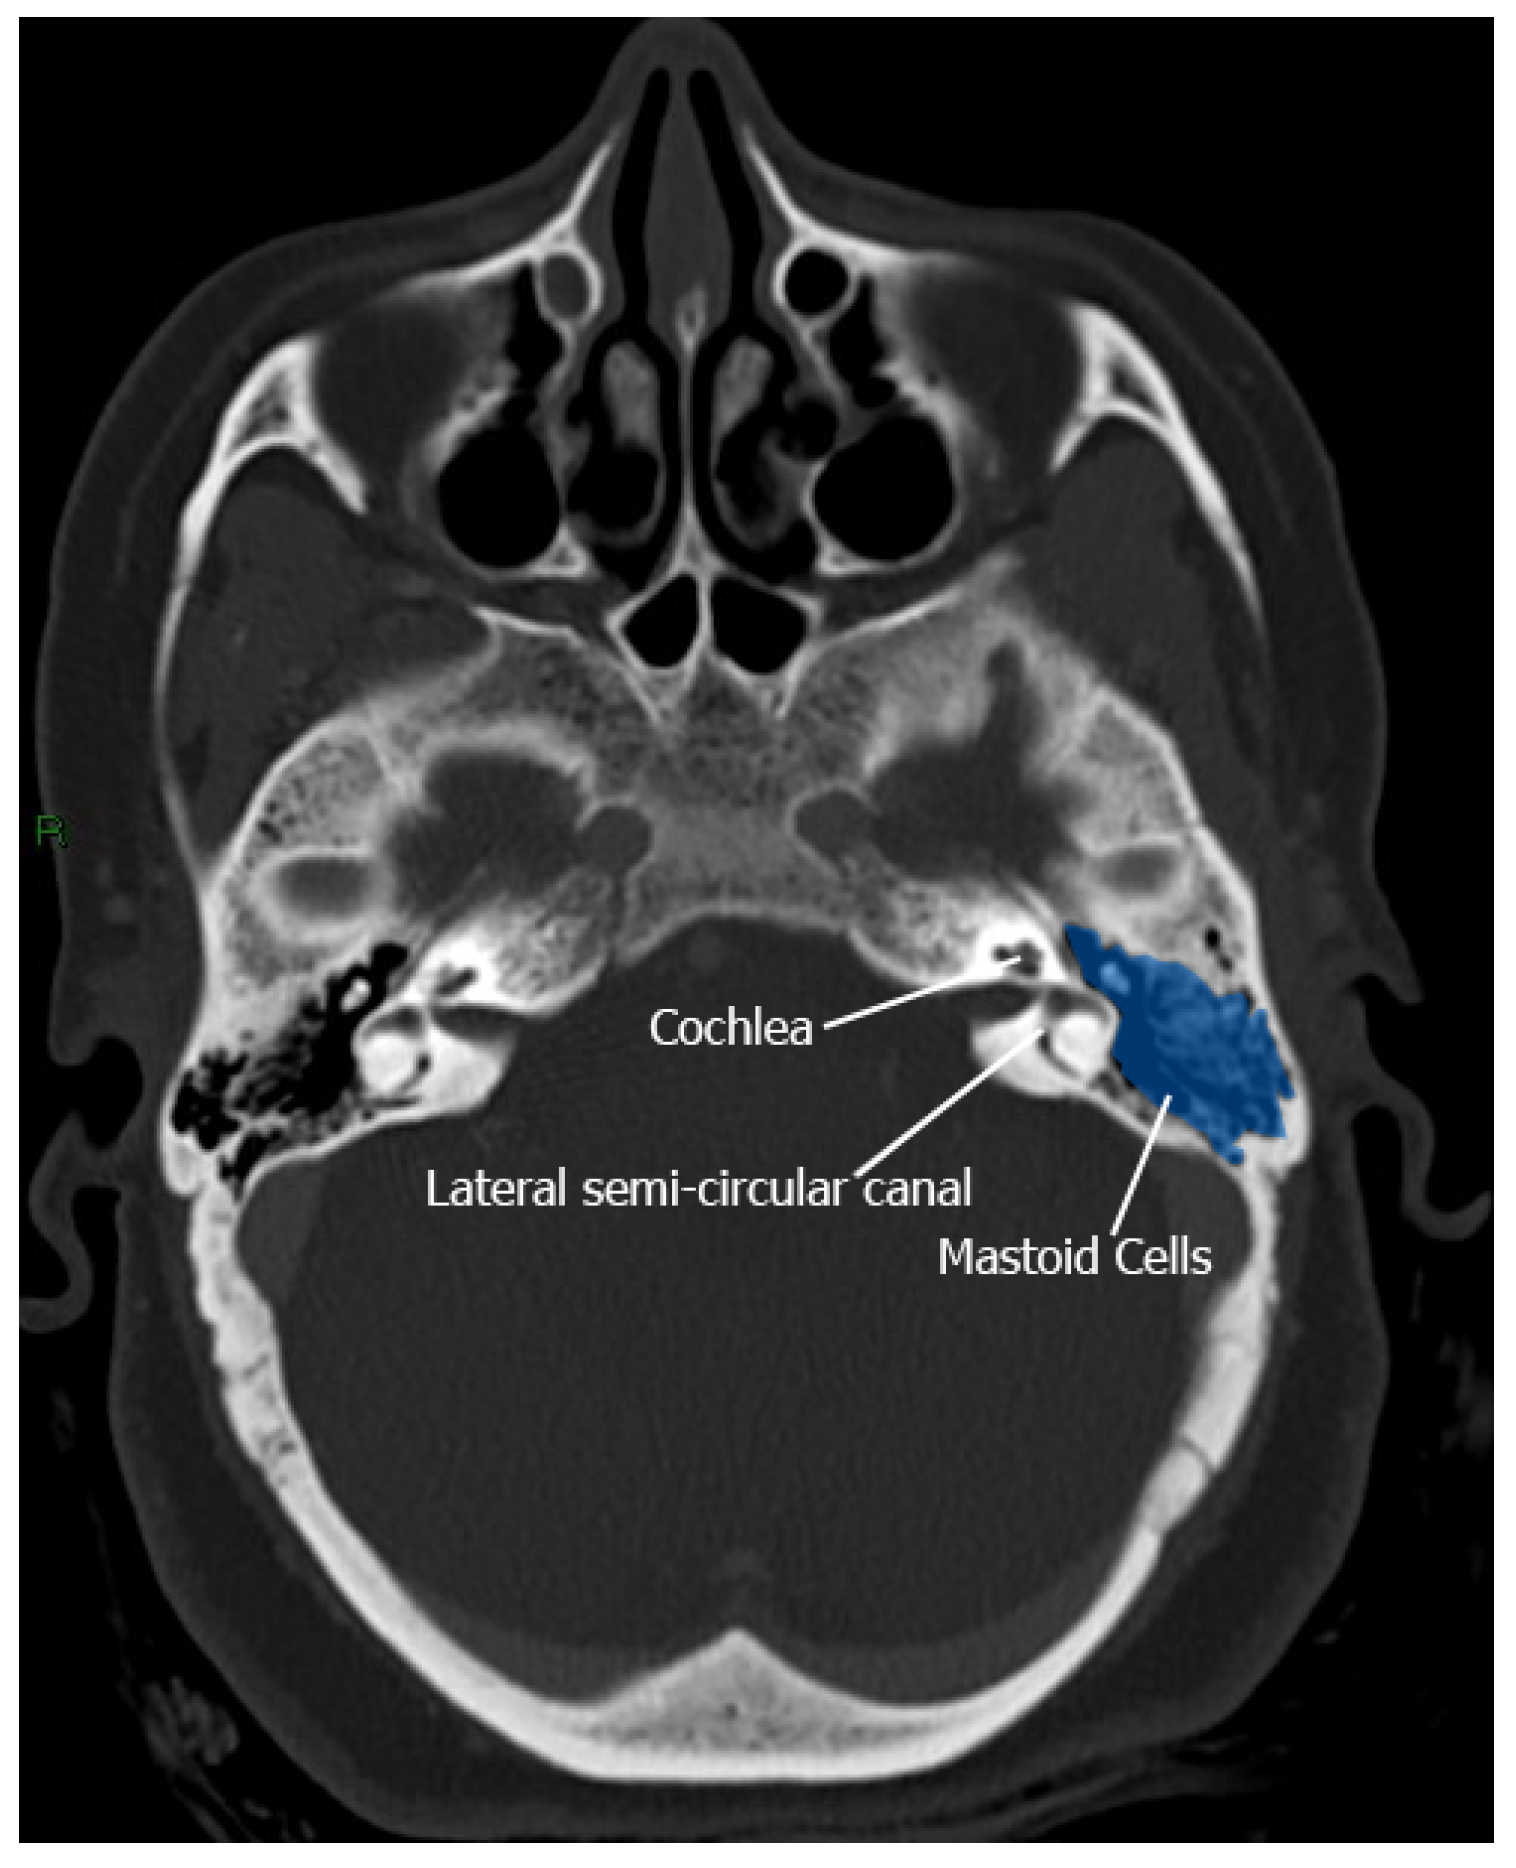

Mastoid Air Cells: The Labyrinthine Thermal Shield

Target Structures: Vitreous and Endolymph